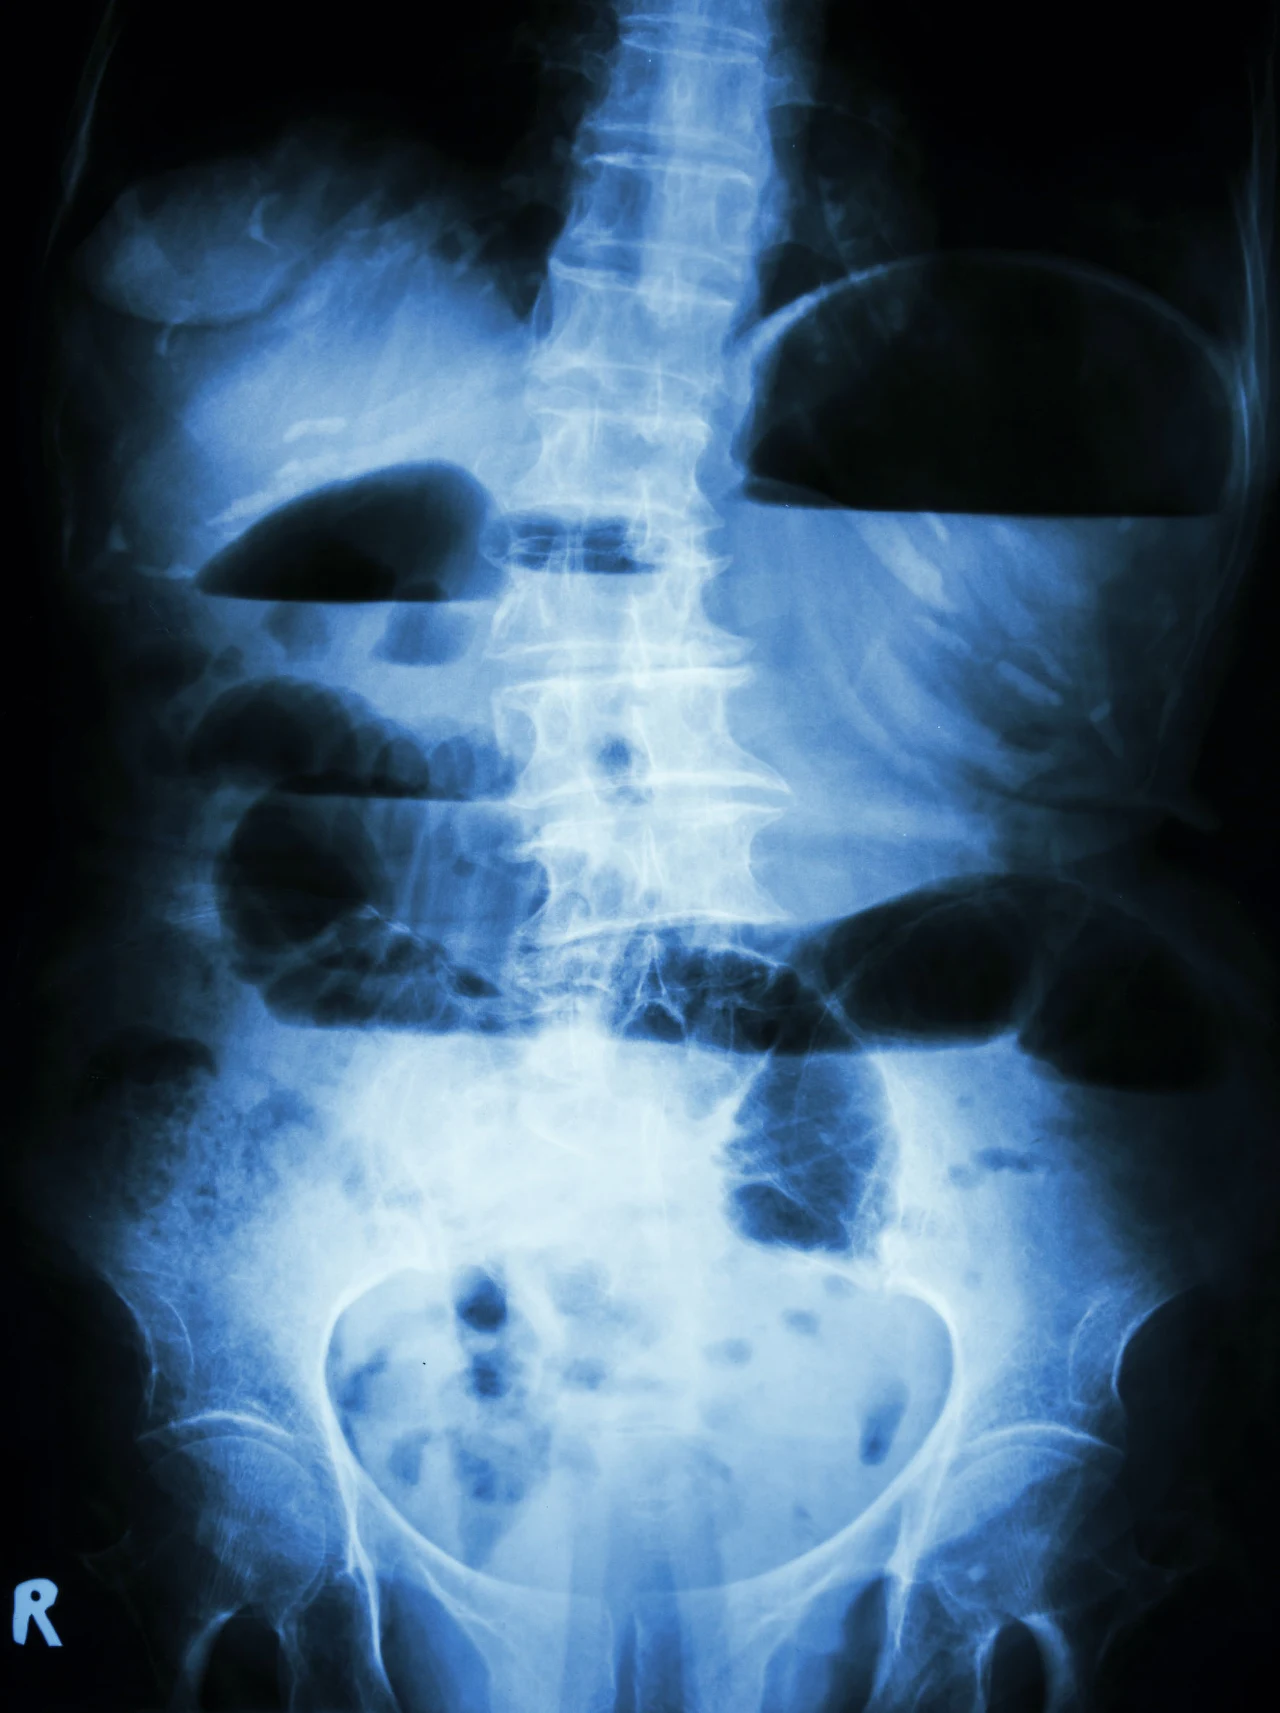

Pierwsze objawy to najczęściej narastający ból brzucha, wzdęcia, mdłości i wymioty. Charakterystyczne stają się też treści zwracane, najpierw pokarmowe, a następnie jelitowe o przykrym zapachu. W dłuższym okresie można odnotować brak stolca oraz pojawienie się gorączki.

Ze względu na charakter niedrożności możemy wyróżnić niedrożność mechaniczną i porażenną. Do przyczyn wywołujących niedrożność jelit mechaniczną należy zatkanie przewodu ciałem obcym, kamieniem żółciowym lub kałowym. Taki sam skutek mogą wywołać polipy oraz guzy nowotworowe jelita i okołojelitowe. Jelito może mieć ograniczoną drożność z powodu zadzierzgnięcia, które może być wywołane przez:

- skręt jelita (skręt esicy)

- wgłobienie jelita

- uwięźniętą przepuklinę

- zrosty w jamie brzusznej.

Niedrożność jelit porażenna spowodowana jest najczęściej zapaleniem otrzewnej, ale także występuje czasowo po przeprowadzonej operacji z otwarciem jamy brzusznej.